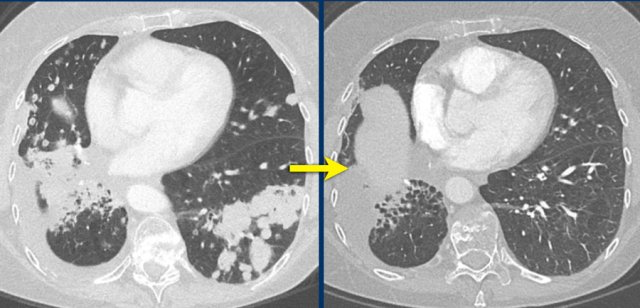

CT images in a 59-year-old female with bone metastases of breast carcinoma during treatment with second line treatment with chemotherapy.

The bone metastases become more sclerotic during treatment, and if you look closely they were already present at the baseline examination.

The lesions do not change in size or number.

This sclerotic change of bone metastases represents a good response.